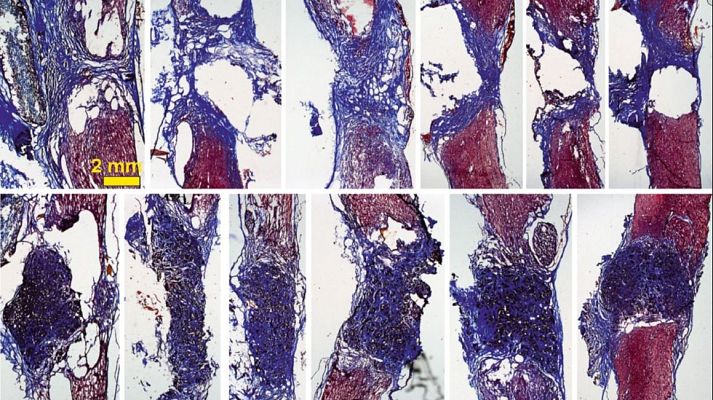

El Consejo Superior de Investigaciones Científicas (CSIC) ha logrado reconectar la columna totalmente partida de una rata. Para llegar a este descubrimiento, los científicos insertaron la espuma de grafeno en médulas dañadas y les sorprendió la capacidad regeneradora de las células. Han sido 10 años de investigación junto al Hospital de parapléjicos de Toledo, donde vieron que los implantes de grafeno servían como soporte para estimular la médula.